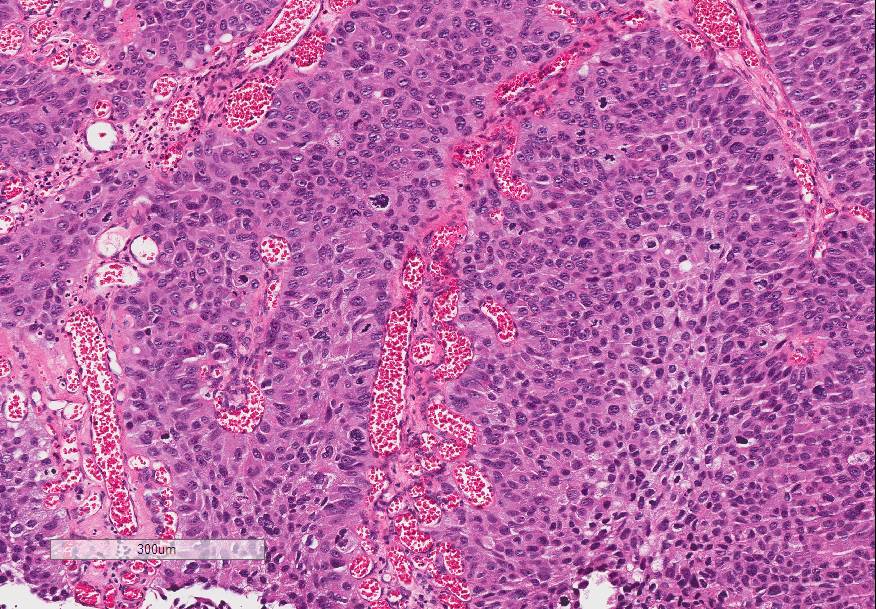

Bladder Papillary Lesions

Case ID: 646